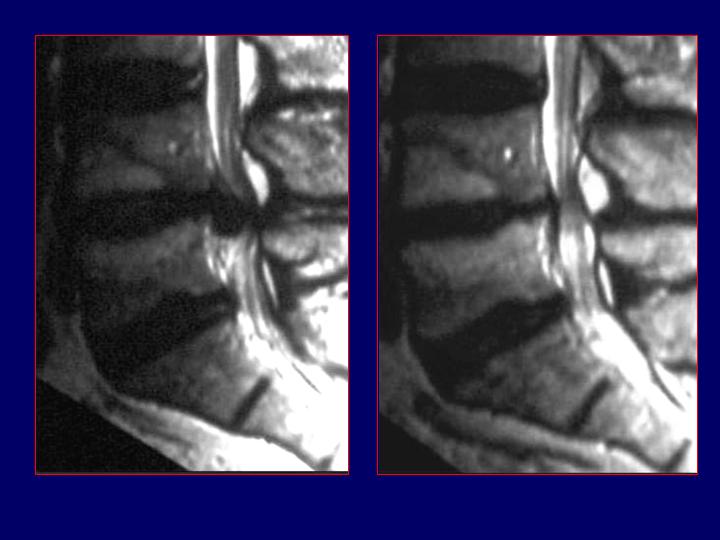

Hernias Discales